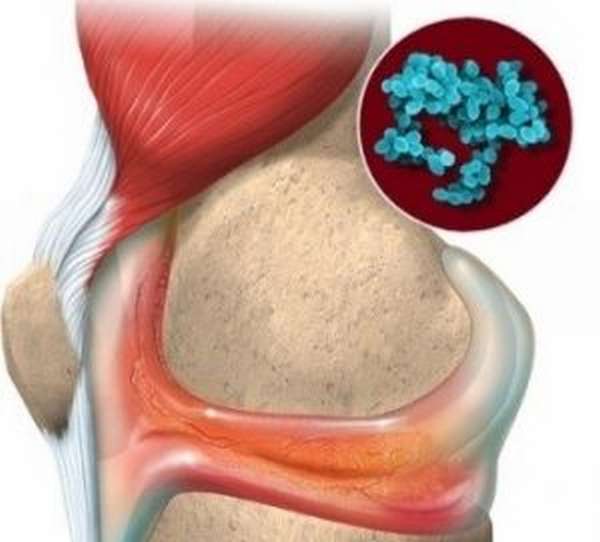

Медицинские состояния: Септический артрит коленного сустава